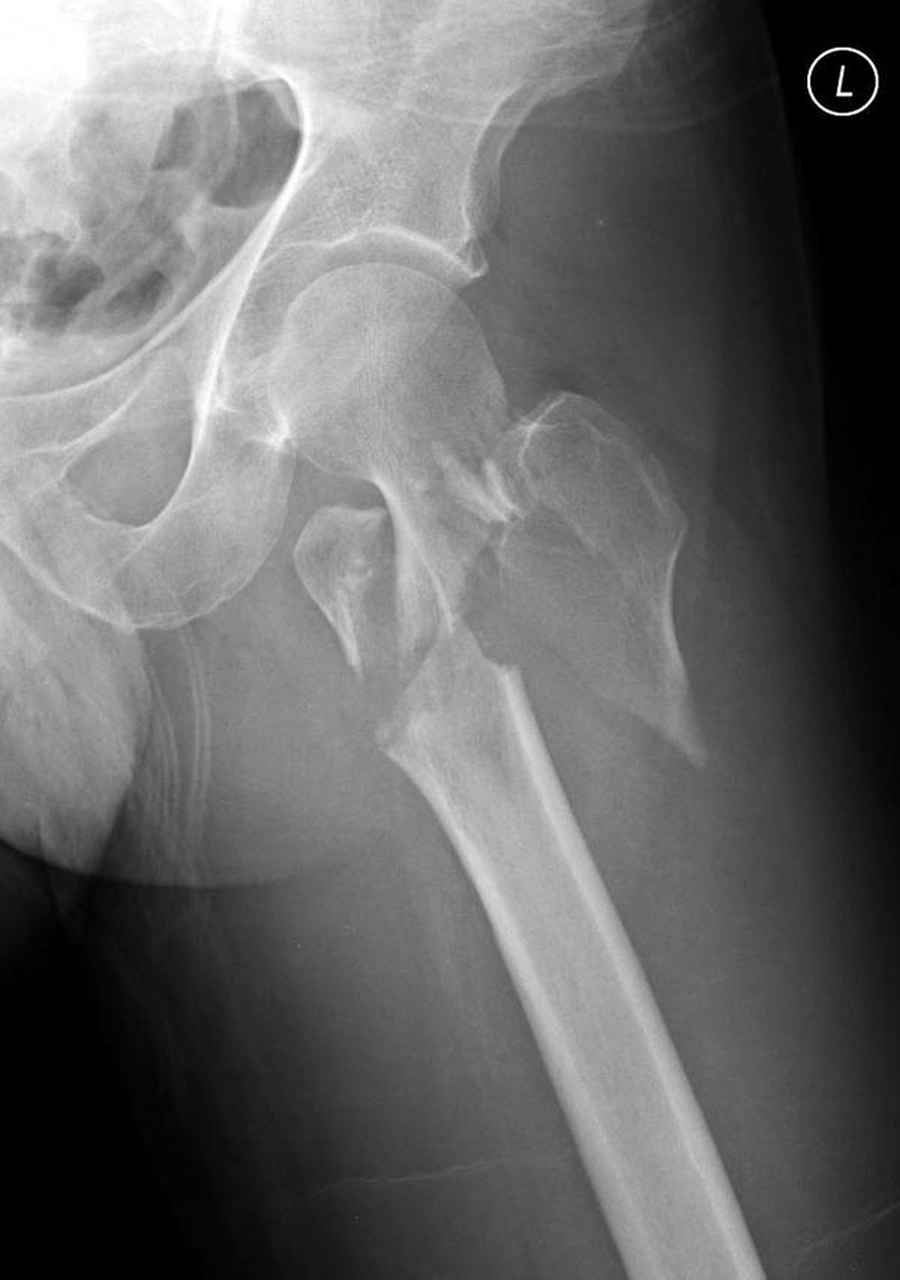

Re: Чрезвертельный перелом бедра

Предлагаемое как вариант консервативное лечение чрезвертельных переломов существует, но это суровое наказание для больного и возврат к прошлому. Такой метод можно предложить, когда невозможно сделать операцию из-за соматического состояния при большом риске от вмешательства.

Для профилактики осложнений нужно как можно быстрее больного ставить на конечность. При лимитированных возможностях подойдут менее щадящие методы, например минимальный гибридный аппарат “шейка-диафиз” или “таз-диафиз”.

Из фиксаторов, мы бы применили цефаломедуллярные, потому что они "по закону моментов" из-за короткого рычага от центра головки к диафизу и по принципу "головка диафиз" механически лучше выдерживают нагрузки, чем пластины.

Но современные пластины с угловой стабильностью не отстают от медуллярных конструкций. Межфрагментарные шурупы и имплант как нейтрализирующее создаст адекватную фиксацию.

Здесь пара случаев фиксации похожих переломов:

первый высокоэнергетическая травма 36 лет